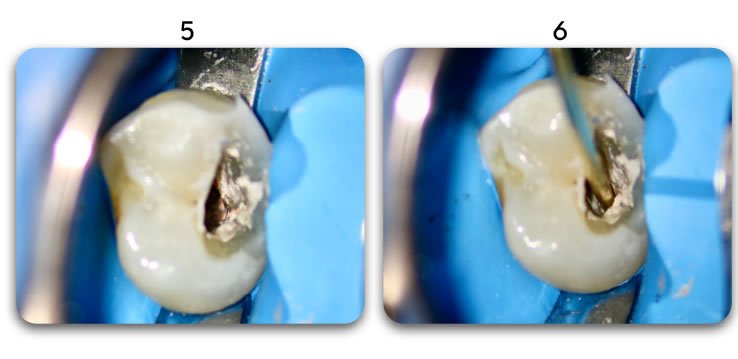

Post removal process:

Use a small round of flame shaped diamond bur to drill in the center of the canal to allow for insertion of a coarse grit ultrasonic tip that will remove remaining cement and post strands.